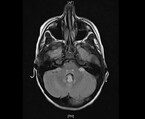

Aus diesem Grund erfolgt am 7. Krankheitstag die Verlegung der Patientin in ein kindernephrologisches Zentrum. Zu diesem Zeitpunkt besteht eine Anurie. Der Hb-Wert beträgt jetzt 8,6 g/dl, im Blutausstrich finden sich Fragmentozyten, die Thrombozyten betragen 44.000/µl. Angestiegen sind die Leukozyten auf 71.700/µl, das Kreatinin auf 5,6 mg/dl, der Harnstoff auf 168 mg/dl und das CRP auf 116 mg/dl. Nach wie vor bestehen eine leichte Hyponatriämie und eine metabolische Azidose. Im Röntgen-Thorax sind ein beidseitiger Pleuraerguss und ein geringes Lungenödem erkennbar (Abb. 1).